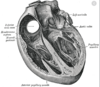

What are coronary arteries?

- arteries supplying the heart with blood

What is the coronary sinus?

- largest vein supplying the heart

- coronary veins drain blood into right atrium

What do the tricuspid and mitral valves separate?

- tricuspid = right atrium and ventricle

- mitral = left atrium and ventricle

When looking at the heart anteriorly, out of the pulmonary veins supplying oxygenated blood from the lungs to the heart, and the pulmonary arteries carrying de-oxygenated blood from the heart to the lungs, which is superior and inferior?

- pulmonary arteries are superior

- pulmonary veins are inferior

What is the sinoatrial node of the heart?

- specialised cardiac muscle

- located in upper wall of atrium

- junction of superior vena cava

- pacemaker of the heart